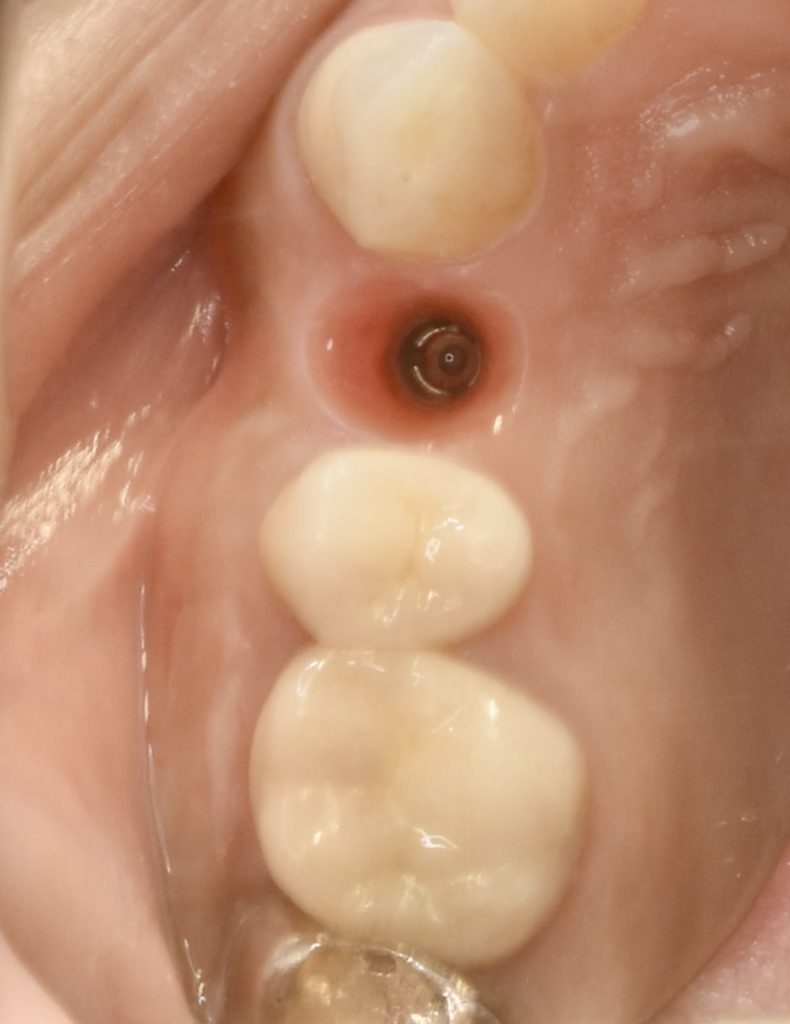

神経がないので痛みというより違和感程度でしたが、抜歯に同意していただき、抜歯と同時にインプラント治療を行い、できるだけ負担を減らし治療期間を短縮する計画を立てました。

この症例にかかる治療期間 約4ヶ月

この症例にかかる費用 約63万円(税別)